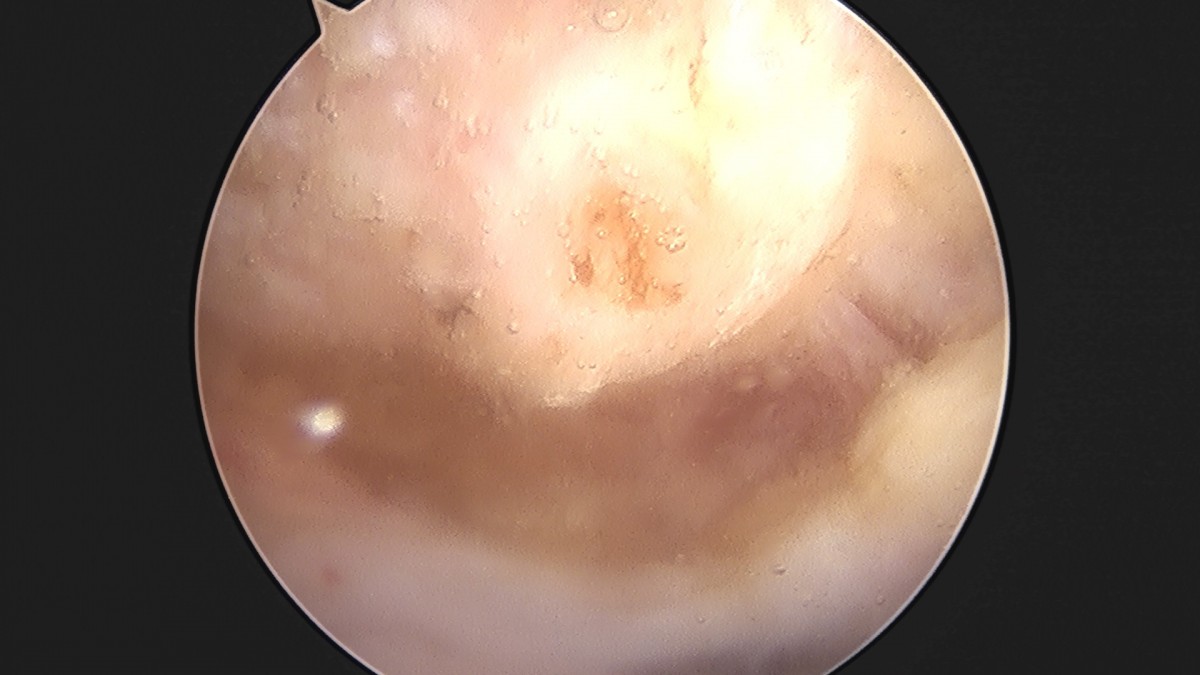

이재상원장님 어깨 견봉하 감압술 이승O 환자

작성자 최고관리자 댓글 0건 조회 806회 작성일 25-09-16 15:26